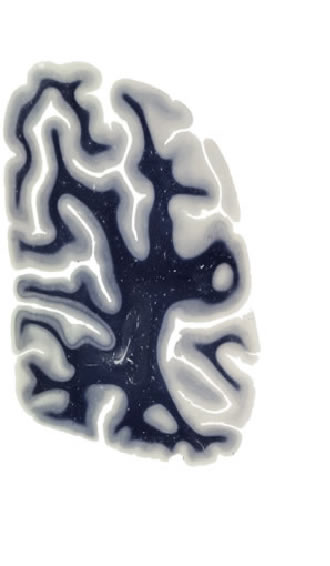

Hi-Resolution Sections · Cells (Nissl Staining) · Virtual Microscopy

Frontal sections (Nissl) from the Atlas Brain:

Macroscopy

Slice ID:

r4-1322

Plate NR:

63

Position:

72,5 mm